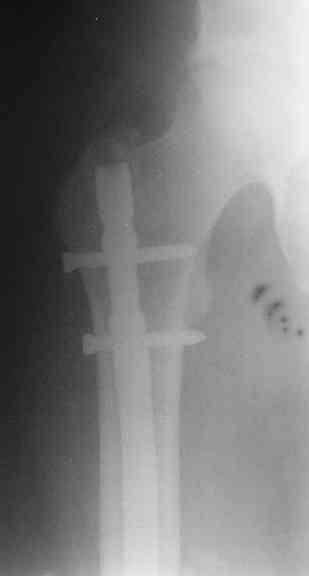

Вот несколько. С тисками и трубой на днях сделаем.

> Вот несколько. С тисками и трубой на днях сделаем.

Саша, последний штифт, пожалуй, перегнули?

> Саша, последний штифт, пожалуй перегнули?

Там заход сделан как для прямого штифта, не через вертел.

И правда, не через вертел. Тогда зачем гнули?